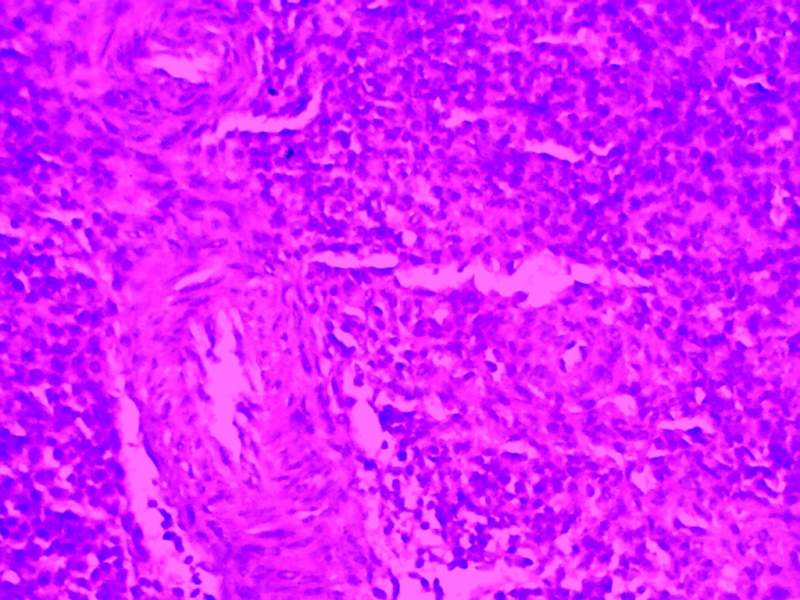

³û¼¦Æ¢ÔàHEȾɫ½á¹û·ÖÎö

ÎÒ×öµÄÊdzû¼¦Æ¢ÔàµÄHEȾɫ£¬Õý³£×éºÍÓв¡×éµÄ 21Óв¡×é-01.jpg 21Óв¡×é-03.jpg 21Õý³£×é+01.jpg 35Óв¡×é-01.jpg 35Õý³£×é+02.jpg |